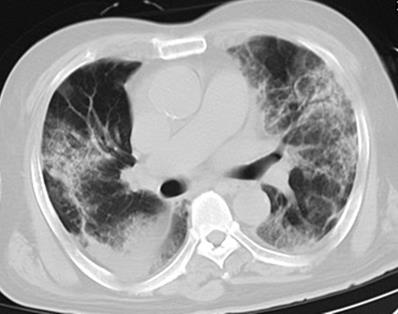

Figure 1

Initial chest CT of a 76-year-old man who presented with fever, cough, and dyspnea for 4 days. Bilateral extensive irregular patchy ground glass opacities (GGOs), strip opacities, consolidation, some with air bronchogram, with both central and peripheral distributions were observed. Mechanical ventilation treatments were used at admission, and the patient died of respiratory failure after 10 days of hospitalization.

As shown in Table 2, all (100%) patients had abnormal CT findings at admission, 210 (94%) patients had bilateral lung involvement, and 102 (45%) patients had more than four lung zones involved. With regard to the distribution of lung lesions, 114 (51%) patients had peripheral distribution, 105 (47%) patients had both central and peripheral distribution, while only 5 (2%) patients had central distribution. Considering lung opacity, 210 (94%) patients had GGO, 46 (21%) patients had consolidation, 37 (17%) patients had GGO with consolidation, 137 (61%) patients had GGO with interstitial thickening, and 38 (17%) patients had air bronchogram (Figure 1, Figure 2). In addition, 2 (1%) patients had lymphadenopathy, and 3 (1%) patients had pleural effusion.